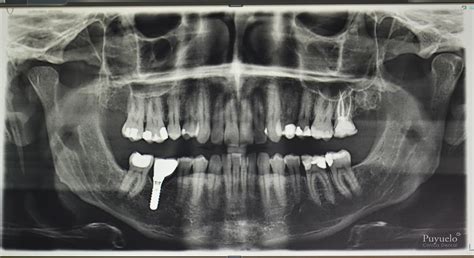

La ortopantomografía, también conocida como radiografía panorámica dental, es una exploración radiológica que permite obtener una visión general de los dientes, el hueso que los rodea y las articulaciones temporomandibulares (ATM). Su nombre proviene del griego, donde la etimología de la palabra viene a ser algo así como la grafía o diseño de un todo en profundidad.

Básicamente, la ortopantomografía es una radiografía frontal en 2 dimensiones de los dientes y los huesos maxilares de un ser humano. La propia definición de este tipo de radiografía ya hace intuir cuáles son las ventajas. No cabe duda de que la principal es la obtención de mucha información en una sola radiografía.

En una ortopantomografía, se pueden observar diferentes tonos que indican distintas estructuras y condiciones:

- Tono gris: Dientes y hueso del paciente. El nivel de hueso se observa a través de una línea gris que recubre parte de los dientes. Si la línea de hueso está por debajo, significa que han habido bacterias debajo de la encía que han ido deteriorándolo.

- Endodoncias: Se observan como dos palitos blancos que rellenan las raíces del diente. Es importante que lleguen hasta el ápice para que no entren bacterias.

- Reconstrucciones: Las reconstrucciones con composite o las restauraciones cerámicas se observan en la parte de la corona de los dientes que han sufrido caries o desgastes.

- Tono negro: Corresponde a todo aquello que no es diente, ni hueso, ni ningún material. Si observamos el color negro en el hueso o algún diente, significará que hay bacterias que los están deteriorando.

Es importante destacar que, si se observa alguna anomalía en la ortopantomografía, será necesario realizar radiografías más específicas en 2D o 3D de la zona afectada para tener la máxima información y poder dar un diagnóstico preciso.